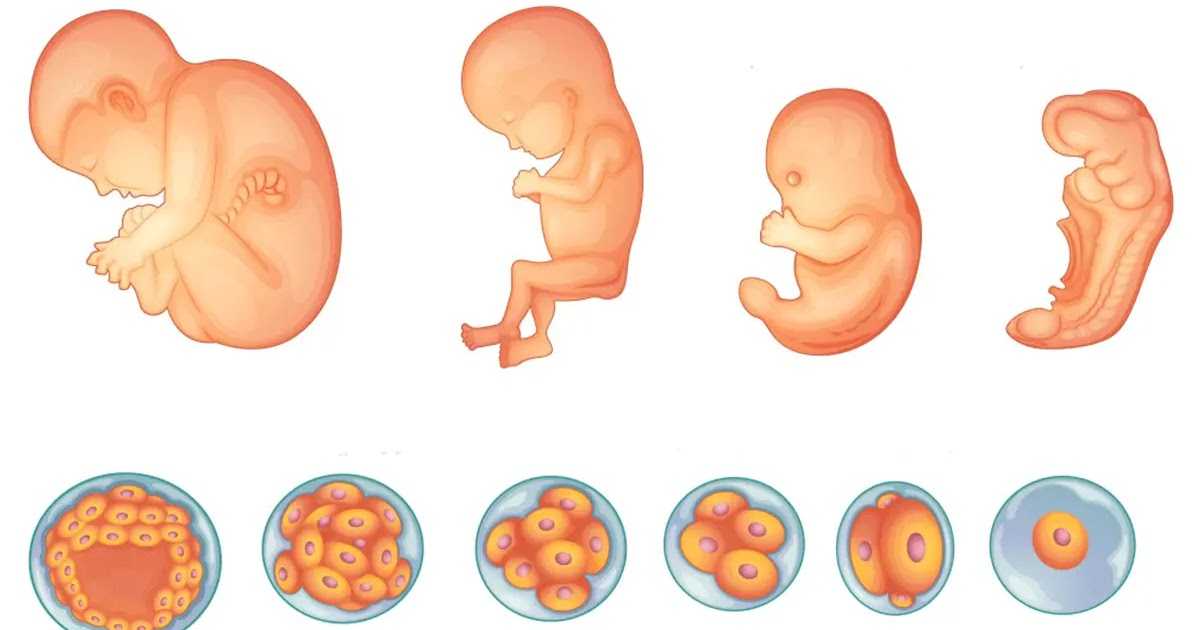

Загадочные образы животных в утробе матери

Раздел: Другие животные